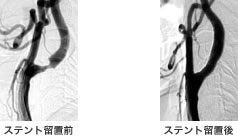

血管内治療(ステント留置術)とは

内科的治療では充分効果の得られない高度な狭窄症に対しては、外科手術(血栓内膜剥離術)が行われ、良好な成績が報告されてきました。

さらに近年、大きな皮膚切開や血管への外科操作が不要な血管内治療と言う治療法が、欧米を中心に発達してきました。これは、細くなって詰まりかけている動脈に対して、血管の中から、風船(バルーン)付きカテーテルを用いて拡張しようというものです。さらにステント(金属の細いワイヤーを編んだような径5-8 mm程の筒で、右の図のように柔らかく血管にフィットする)を拡張したあとに留置してきます。ステントは一生血管内で血管を拡張し続け、再狭窄を予防するとともに、血管の内側に新たな膜を形成し、動脈硬化巣を安定させる働きがあります。

麻酔は穿刺部(大腿部または肘部)の局所麻酔と鎮静剤で済み、頸部の皮膚切開は不要です。要する時間は2-4時間程です。